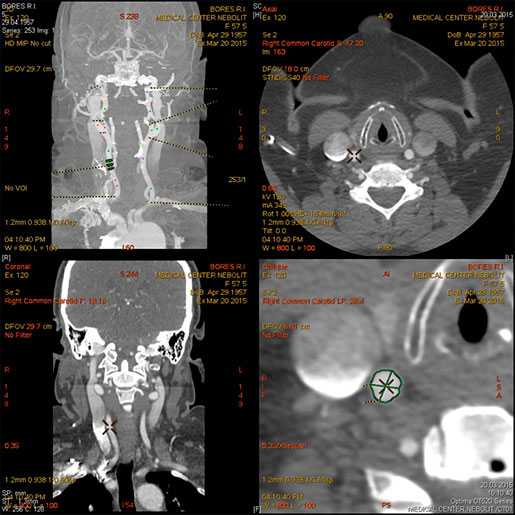

МСКТ-ангиография сосудов головного мозга

МСКТ высоко чувствительна в диагностике атеросклеротических кальцинированных, ,,мягких,, бляшек. В большинстве клиник метод МСКТ стал основным методом диагностики заболеваний сосудов сонных артерий, грудной, бюшной аорты, периферических пртерий.

Показания:

- диагностика сосудистых заболеваний (аневризмы, стенозы, мальформации, аномалии развития)

- Выявление венозного тромбоза

- Подозрение на острое кровотечение